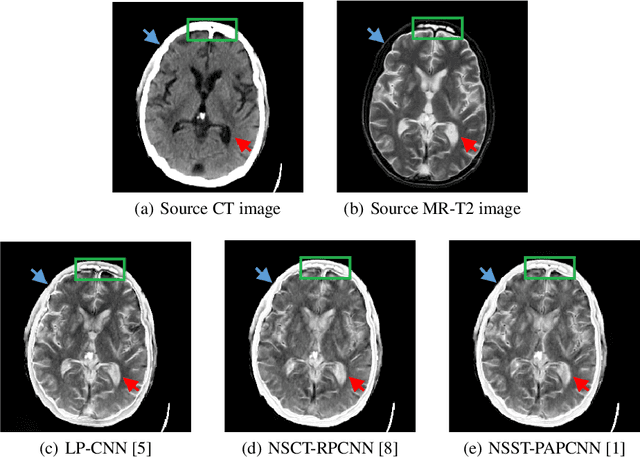

Abstract:It is necessary for clinicians to comprehensively analyze patient information from different sources. Medical image fusion is a promising approach to providing overall information from medical images of different modalities. However, existing medical image fusion approaches ignore the semantics of images, making the fused image difficult to understand. In this paper, we put forward a semantic-based medical image fusion methodology, and as an implementation, we propose a Fusion W-Net (FW-Net) for multimodal medical image fusion. The experimental results are promising: the fused image generated by our approach greatly reduces the semantic information loss, and has comparable visual effects in contrast to the state-of-art approaches. Our approach and tool have great potential to be applied in the clinical setting. The source code of FW-Net is available at https://github.com/fanfanda/Medical-Image-Fusion.